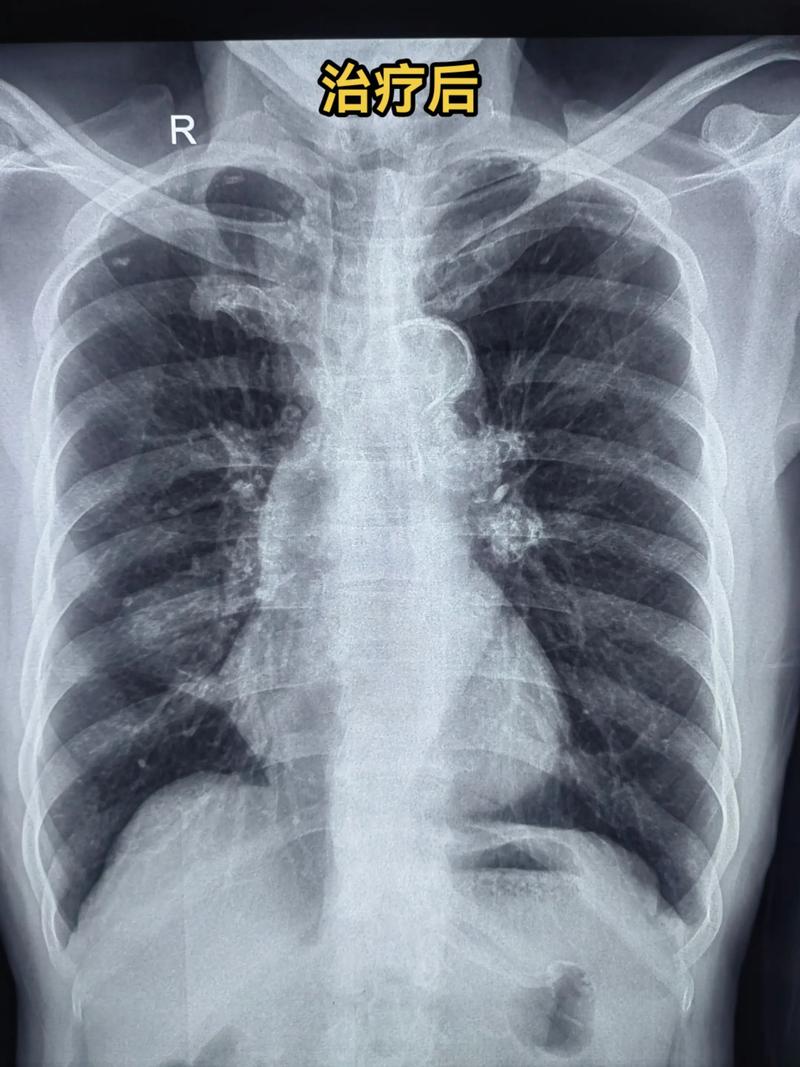

(图片来源网络,侵删)- 原因:可能与严重感染、缺氧、心力衰竭、凝血功能障碍等有关。

- 表现:病情危重,气管内可吸出或口鼻涌出鲜血样液体,X光上肺部会呈现大片实变影。

- 预后:非常凶险,需要立即进入重症监护室进行抢救。